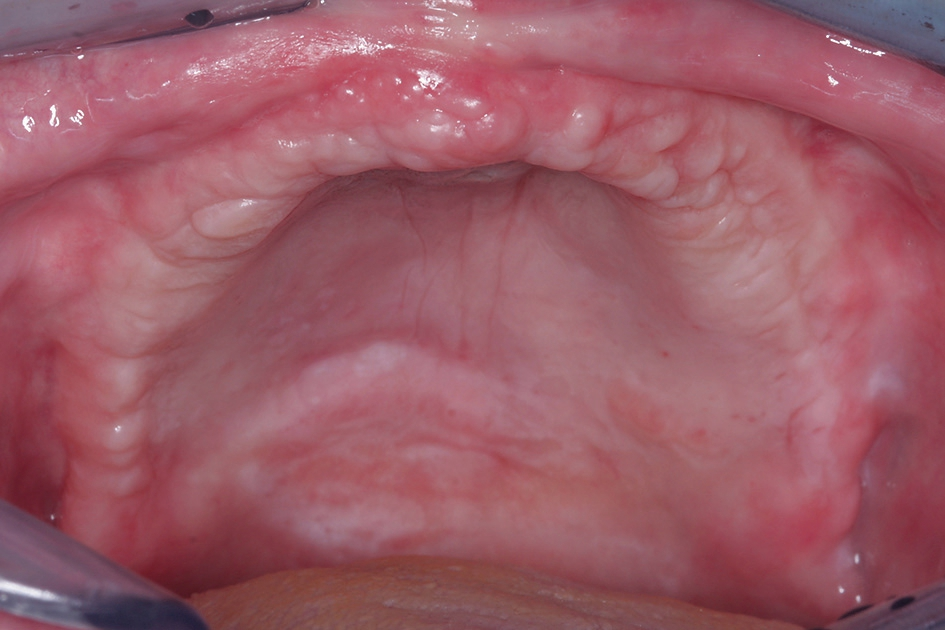

Der vorliegende Fall beschreibt die orale Rehabilitation einer 65 Jahre alten Patientin im Oberkiefer (Abb. 1 und 2). Der atrophierte Oberkiefer weist eine sagittale Stufe zum Unterkiefer auf. Dies macht eine komplett festsitzende Versorgung von vorneherein schwer umsetzbar. Die Patientin wünschte sich dennoch einen ästhetisch ansprechenden Zahnersatz und eine langzeitstabile Lösung. Die konservierende Behandlung des Unterkiefers wurde im Rahmen der ganzheitlichen Sanierung von uns ebenfalls geplant und durchgeführt.